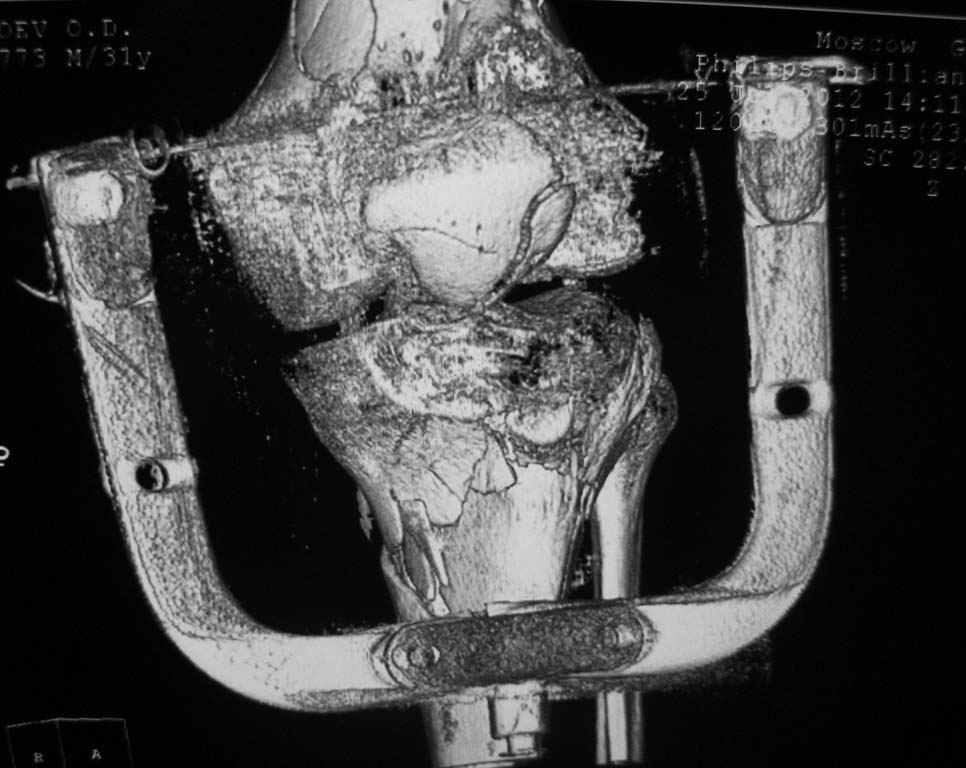

Нужен совет. Открытый перелом в\3 диафиза с оскольчатым переломом дистального метаэпифиза бедра. Закрытый оскольчатый внутрисуставной перелом проксимального отдела большеберцовой кости той же конечности.

При поступлении ПХО ран, скелетное вытяжение. Рана зажила первичным натяжением. Осложнилось правосторонней пневмонией. Предстоит выбрать тактику оперативного лечения и камими имплатнатами.